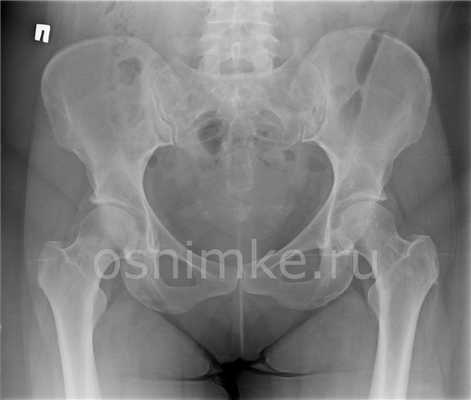

Какие инструментальные методы исследования привлекаются в диагностике подвывиха тазобедренного сустава? Прикладной является рентгенография сустава в двух проекциях. На рентгенологических снимках выявляют смещение головки плечевой кости из вертлужной впадины. Этого метода достаточно, чтобы выявить нарушение и определиться с нюансами врачебной тактики.

Методом выбора является рентгенография тазобедренного сустава в прямой и боковой проекциях. Это позволяет исключить переломы. Однако, в некоторых случаях, даже если рентгенологическая картина в норме, требуется проведение дополнительных исследований, например, КТ или МРТ тазобедренного сустава, с целью исключения скрытых переломов или повреждения мягких тканей.

В сложных случаях КТ может быть полезна для получения дополнительной информации, которая необходима при планировании операции. Также стоит учитывать, что интерпретация рентгеновского снимка будет осложнена у пожилых людей наличием других состояний, например, дегенеративных процессов.

Рентгенограмма как метод исследования рассчитана на визуализацию костных структур. При диагностике хорошо просматриваются:

- Кости таза. Видны анатомические дефекты, переломы, трещины, асимметрия.

- Сустав. Выявляют вывихи, подвывихи, расширение суставной щели, сужение или сращение с формированием анкилозов.

- Головка бедренной кости. Просматривается вертел, шейка бедра, выявляются трещины, переломы, аномалии развития и строения, остеомиелитные и остеопорозные изменения.

Рентген тазобедренных суставов проводится в двух проекциях, которые помогают расширить визуализируемую анатомическую область и точно определить объем поражения:

- Передняя проекция. Пациента укладывают на спину, ноги разводят максимально в стороны, что позволяет раскрыть сустав и увеличить площадь диагностики.

- Боковая проекция. Пациент ложится на бок, вытягивает ноги вперёд.